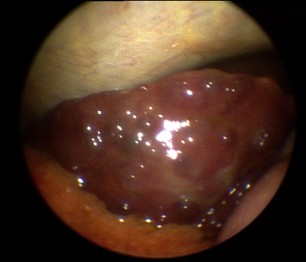

Leberzirrhose bei autoimmuner Hepatitis